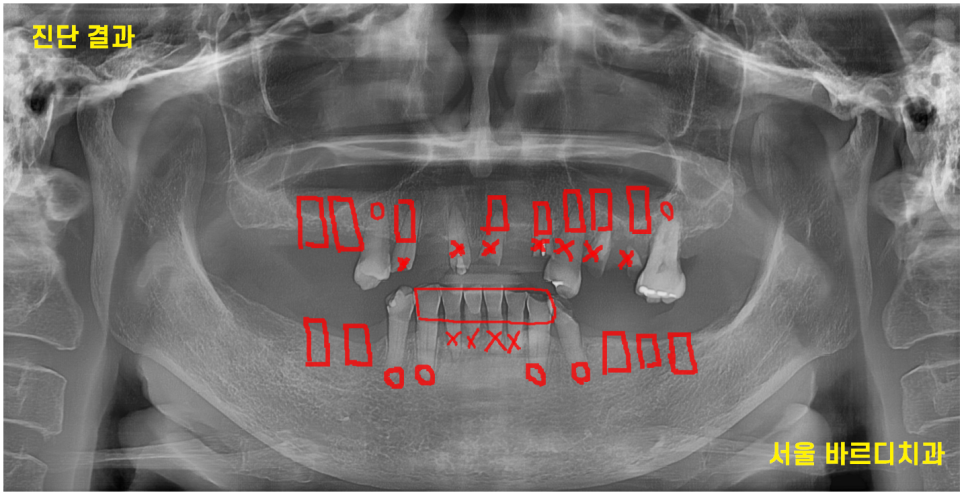

초진 내원 시 찍은 파노라마 사진입니다.

한눈에보기에도 치아가 부러지고

몇개 안남아 있죠~?

230817